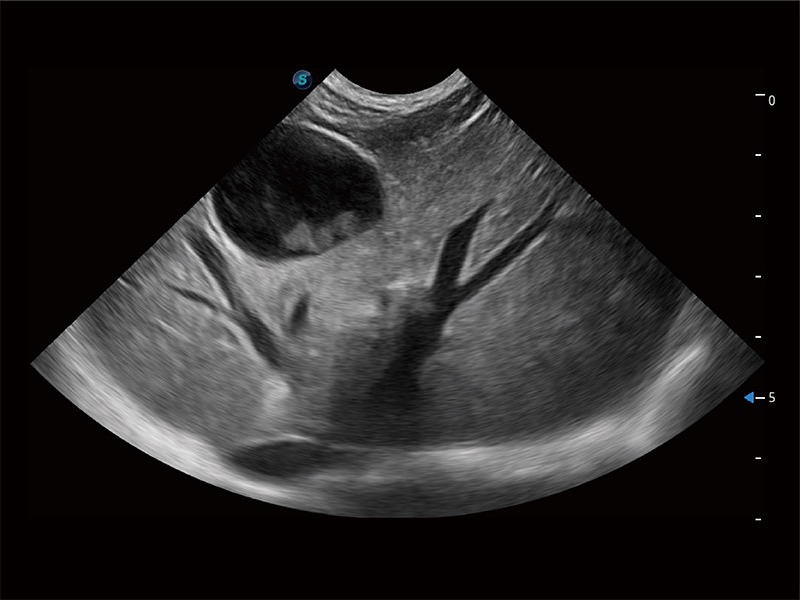

ProPet 80 配备了丰富的心脏探头群、先进的成像技术和专业的心脏测量工具,可帮助动物医生为不同体型和生理结构的动物提供心脏和心肌功能的全面评估。

实时用颜色表示心肌组织运动,观察和定量组织的运动情況,对快速检测与评估心肌的灌注和活性、电传导及心肌收缩和舒张功能等均能提供重要的诊断信息。

通过心肌识别技术与二维斑点追踪技术相结合,对心脏的超声图像进行量化分析。计算心肌17个节段的应变、应变率、速度、位移等,并通过牛眼图的形式进行呈现。

通过360度任意调节3条M型取样线,在同一心动周期上观察心脏不同位置的运动曲线,得到准确的心功能测量数据,有效评估心肌运动及左心室功能。

具备多种协议可选,同时支持17阶段划分法和专业的SE报告。

能够增加心肌组织与血流之间的区别。对于心脏扫查困难的动物,可提供更好的心内膜边界的显示。

能够基于左心室壁追踪和辛普森法,自动计算射血分数,支持多个可移动点描迹,与手动测量相比,极大节省了动物医生的时间和精力。